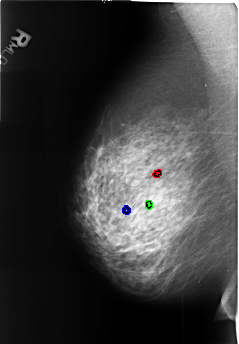

B_3449_1.RIGHT_MLO

FILE: B_3449_1.RIGHT_MLO.OVERLAY

TOTAL_ABNORMALITIES 3

ABNORMALITY 1

LESION_TYPE CALCIFICATION TYPE LUCENT_CENTERED DISTRIBUTION N/A

ASSESSMENT 2

SUBTLETY 3

PATHOLOGY BENIGN_WITHOUT_CALLBACK

TOTAL_OUTLINES 1

ABNORMALITY 2

ABNORMALITY 3